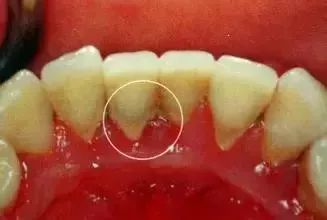

2牙结石

牙结石是指沉积在牙面上的矿化的菌斑,根据其沉积部位和性质分为龈上牙结石和龈下牙结石两种。

位于龈缘以上的牙面上,肉眼可直接看到。在牙颈部沉积较多,如上颌磨牙的颊侧和下颌前牙的舌侧沉积更多。龈上牙石中无机盐的主要来源是唾液中的钙、磷等矿物盐。